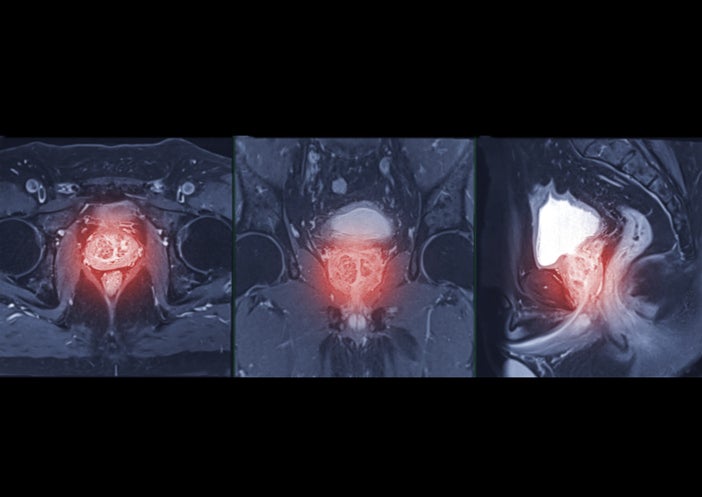

It happens almost exclusively after prostate related surgeries, the bulk of which are prostatectomies to remove the prostate for prostate cancer and then to a lesser extent procedures to treat enlarged prostate. Radiation for pelvic cancers can be a risk factor as well.

• One surgical treatment procedure I offer is a sling that some men who have mild to moderate incontinence can consider if they have not had a history of radiation. During the procedure, a synthetic mesh is strategically positioned around the urethral bulb. The sling compresses the urethra and sphincter, effectively displacing it to a modified and desired location.

• For men who have been radiated or who have moderate to severe incontinence, an artificial urinary sphincter (AUS) is the gold standard surgical treatment option for incontinence in men. An AUS is a device that uses an inflatable cuff to control urine flow. This cuff is positioned around the urethra, the tube that carries urine from the bladder out of the body, near its junction with the bladder. A separate balloon placed in the abdomen regulates the pressure and tightness of the cuff, effectively acting as a valve to control urine release. A simple pump placed in the scrotum allows a man to open the AUS, as needed, to empty the bladder. It is important that patient’s have the dexterity and cognitive ability to manage the device prior to considering implantation.